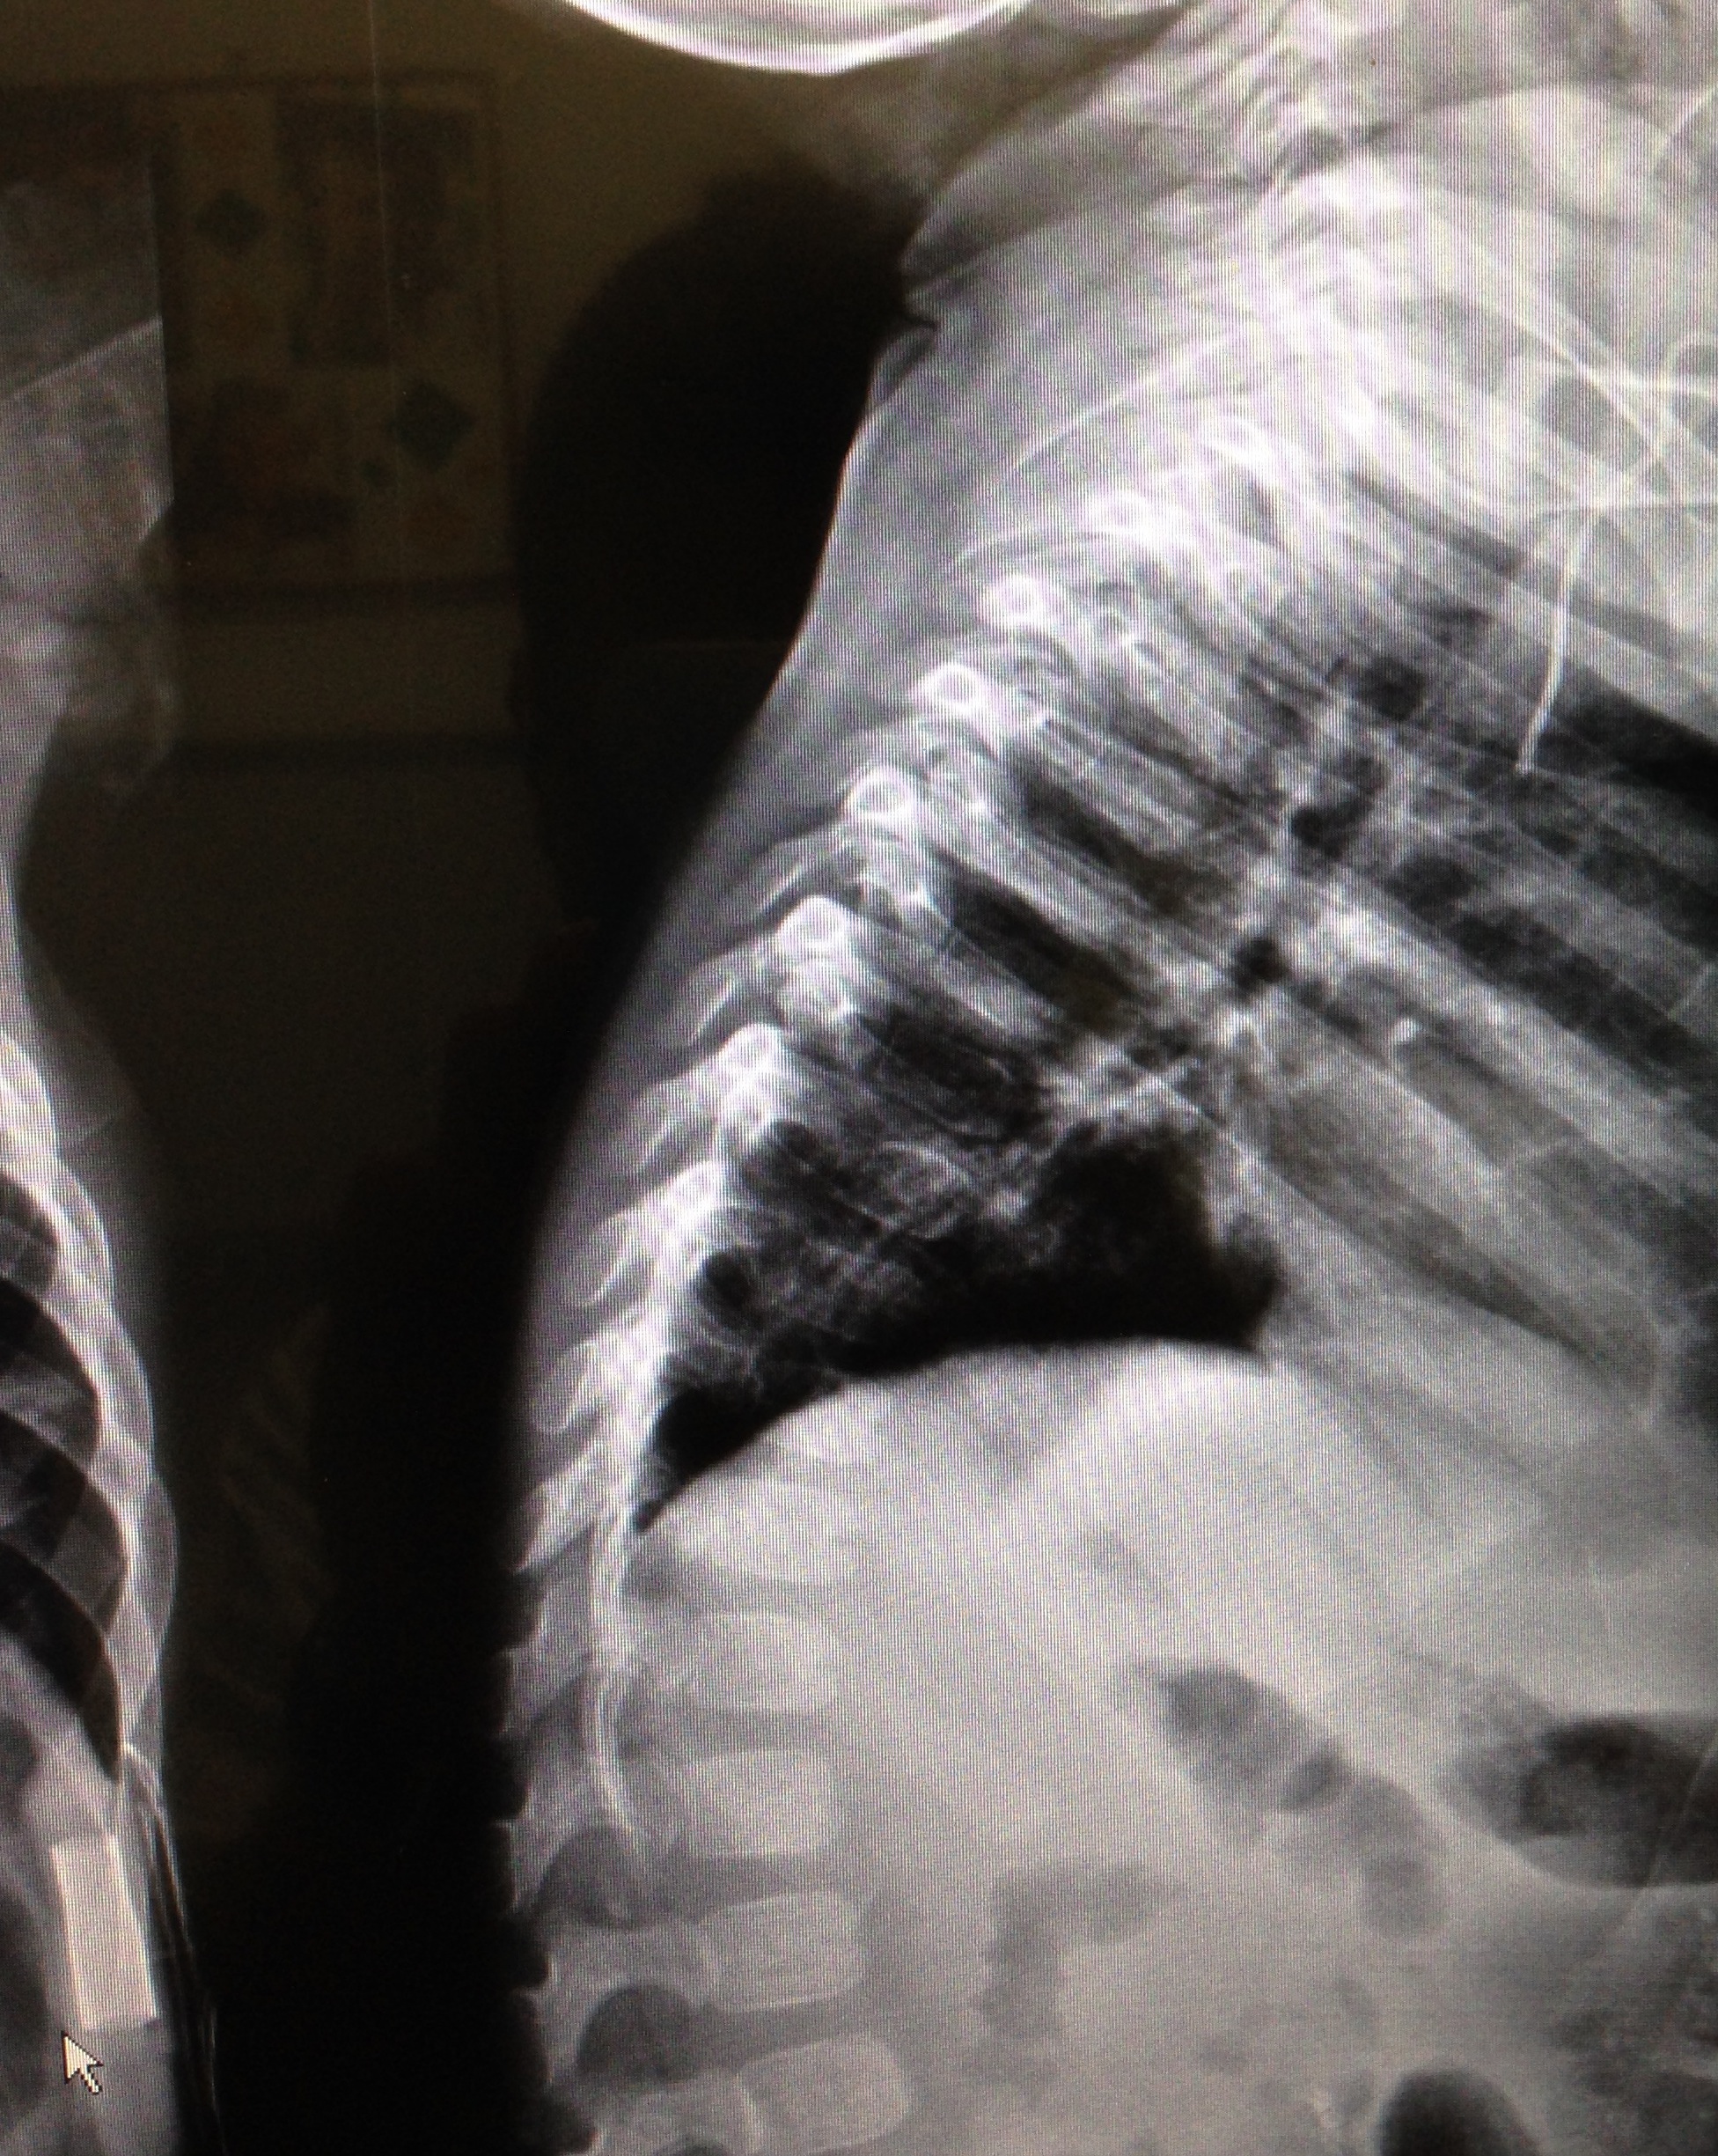

In sesta giornata si assiste a un drammatico scadimento delle condizioni generali; condotto in Pronto Soccorso presenta iporeattività, pallore, apiressia, tachidispnea (70 atti per minuto), tachicardia (180 bpm) con III tono udibile e saturazione O2 = 95%. Al torace murmure vescicolare assente e rantoli grossolani in basale sinistra. Addome trattabile. Si pratica in urgenza Rx torace: “emitorace sinistro occupato da multiple immagini aeree con cancellazione del profilo diaframmatico omolaterale; sbandamento mediastinico controlaterale” (Figura 1). Consulenza cardiologica con ecocardiografia: “Lieve scollamento pericardico; insufficienza tricuspidalica”.